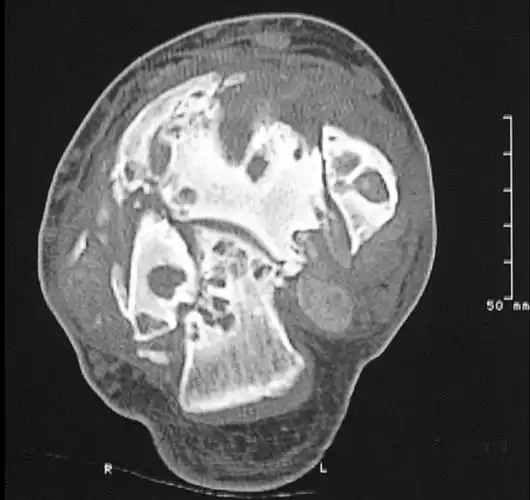

神经性关节病患者的踝关节ct扫描,注意关节面破坏,关节的解体和破碎